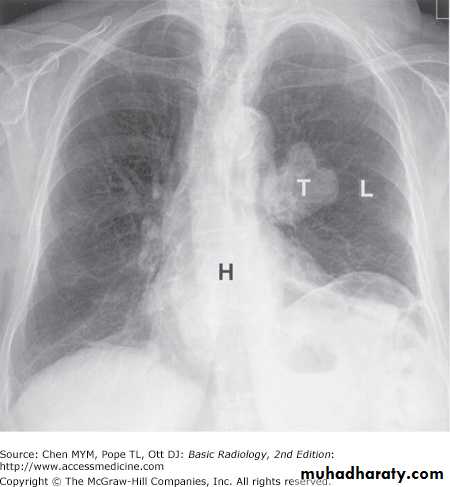

Conventional radiography refers to plain radiographs that are generated when x-ray film is exposed to ionizing radiation and developed by photochemical process. During development, the metallic silver on the x-ray film is precipitated, rendering the latent image black. The amount of blackening on the film is proportional to the amount of x-ray radiation exposure. Plain radiography relies on natural and physical contrast based on the density of material through which the x-ray radiation must pass. Thus, gas, fat, soft tissue, and bone produce black, gray-black, gray, and white radiographic images, respectively, on filmAlthough other image modalities such as CT, ultrasonography, and MR imaging are being used with increasing frequency to replace plain radiographs, conventional radiography remains a major modality in the evaluation of chest, breast, bone, and abdominal diseases